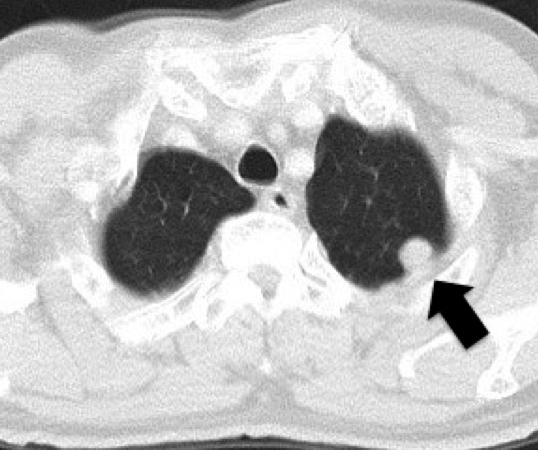

術後経過:術後補助化学療法は施行せず,1か月ごとに外来フォローを行った.2017年8月(術後17年6か月),胸部CTで左上葉に13 mmの円形腫瘤影を認め(Fig. 3),残肺再発と診断した.頭部CTを施行したが,脳転移の所見は認めなかった.2017年9月(術後17年7か月)に胸腔鏡下左上葉S1+S2腫瘍切除を施行した.病理組織学的検査で中心部に壊死を伴って癒合性の異型腺管を形成し,浸潤性に増殖する管状腺癌像を認めた.免疫染色検査では,初回肺手術と同様の染色パターンを示し,直腸癌の肺転移と診断した.2018年6月(術後18年4か月)CTで縦隔リンパ節腫大を認め,縦郭リンパ節転移と診断し,カペシタビンの投与を行った.2018年9月(術後18年7か月)よりふらつき,四肢の運動障害を認めるようになり,頭部MRIを施行したところ,多発脳転移(6か所)を認めた(Fig. 4).経過中に四肢麻痺や失語,嘔吐が出現したためカペシタビンは中止し,2018年10月(術後18年8か月)ガンマナイフ治療を行った.ガンマナイフ施行後より意識状態の著明な改善,右上下肢の筋力改善を認めた.自力での経口摂取可能,発語可能となりQOLの改善を認めたが,直腸癌手術から19年後,初回肺切除術より2年2か月後に癌死した.

Chest CT scan 7 months after left lower lobectomy showed a new lesion in the upper lobe of the left lung (arrow).